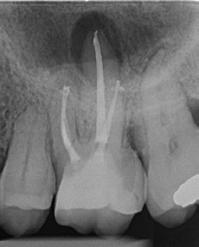

1. ábra: A 15-ös foggyökér meziális felszíne mellett látható radiolucens elváltozás, illetve a felvételen látható a korábban behelyezett gyökértömés, a parapulpális csap segítségével elhorgonyzott csonkfelépítés és a fogat borító cirkonkorona. –2. ábra: A saggitalis irányú CBCT-metszeten jól megfigyelhető az állcsontgerincet elérő radiolucens elváltozás. – 3. ábra: Az axiális irányú CBCT-metszeten egyértelműen látható a kezeletlen palatinális gyökércsatorna, valamint a radiolucens elváltozás mezio-disztális kiterjedése is jól megítélhető. – 4. ábra: A palatinális gyökércsatorna szelektív endodonciai kezelése során először gyógyszeres zárás került behelyezésre. – 5. ábra: A gyógyszeres zárás során alkalmazott kalcium-hidroxid alapú paszta a szulkuszon keresztül a szájüregbe extrudálódott. – 6. ábra: A gyökértömő anyag a középső és apikális gyökéri harmad határán lévő laterális csatornán keresztül a periapikális térbe extrudálódott. 7. ábra: A kezelések befejezését követően 4 évvel készült röntgenfelvételen jól látható a csontállomány gyógyulása és a fiziológiás gyökérhártyarés újbóli kialakulása. –8. ábra: A peroperatív CBCT-felvétel alapján készített koronális irányú metszeten jól látható a gyökércsúcs körül lévő periapikális felritkulás. – 9. ábra: A kezelések befejezése után 4 évvel készített CBCT-felvételen a gyulladásos lézió teljes megszűnése észlelhető.

A CBCT-készülékek endodonciai alkalmazásának talán az az egyik legnagyobb előnye, hogy így olyan anatómiai struktúrák is láthatóvá válnak, amelyeket egyébként nem tudnánk detektálni panoráma, cephalo, vagy periapicalis felvételek segítségével. Mivel a CBCT-felvételek kiértékelése számítógép segítségével történik, így a felvételek vizsgálata során lehetőségünk van az adott területet több nézőpontból és több síkban is megvizsgálni. 2015 októberében egy korábban a rendelőnkben kezelt 55 éves férfi páciens azzal a céllal kereste fel ismét a rendelőnket, hogy másodvéleményt kérjen egy jobb felső kvadránsban található fogával kapcsolatban. Egy másik rendelőben történő vizsgálat során a panaszos fog törését vélelmezték és a fog eltávolítását javasolták, illetve arról is beszámolt, hogy az elmúlt hét során ezen a területen egy puha duzzanat is kialakult. A klinikai vizsgálat során a jobb felső első és második kisőrlő között (14–15) egy fluktuáló duzzanatot észleltünk az áthajlásban. Az 15-ös fog mesialis oldalán 12 mm mély tasakot szondáztunk. A páciens által hozott periapicalis felvételen a 15-ös fog gyökércsúcsának mesialis részén egy nagy kiterjedésű radiolucens elváltozás volt észlelhető (1. ábra). A saggitális síkban vizsgált CBCT-felvételen (Carestream CS 9000, Carestream Dental) a lézió valódi kiterjedése is láthatóvá vált (2. ábra). A megelőző endodonciai kezelések során csupán a bukkális csatorna került detektálásra és gyökértöméssel való ellátásra. Az axiális irányú CBCT-szeleteken egyértelműen látható volt az ellátatlan palatinális gyökércsatorna (3. ábra)

A buccalis csatornába üvegszálas csapot helyeztek, amely a csonkfelépítés elhorgonyzását biztosította. A pácienst arról is tájékoztattuk, hogy egy ferdén behelyezett fém parapulpális csap perforálta a fog koronáját és a csap vége eléri a parodonciumot. A páciens tájékoztatását követően az a döntés született, hogy célszerű lenne a palatinális gyökércsator-

na szelektív endodonciai kezelésének elvégzése. A páciens a javasolt kezelési tervet elfogadta.

Először kalcium-hidroxid alapú ideglenes gyógyszeres zárás került a palatinális csatornába (UltraCal XS, Ultradent Products; 4–5. ábra), amelyet 6 hét után a végleges gyökértömés elkészítése előtt eltávolítottunk. A gyökértömés elkészítése során meleg vertikális kondenzációs technikát alkalmaztunk. Radiológiai felvételen megfigyelhető volt, hogy a gyökértömő anyag egy laterális csatornán keresztül kis mennyiségben a periapicalis térbe extrudálódott (6. ábra). A 4 évvel később készített kontrollfelvételeken a lézió gyógyulása volt megfigyelhető (7–9. ábra). A vizsgálati eredmények és a kezelés kimenetele egyértelműen igazolta, hogy nem gyökérfraktúrával álltunk szemben, tehát a kezdeti diagnózis tévesnek bizonyult. Ez is azt erősíti, hogy korlátozott mennyiségben rendelkezésre álló adatok alapján nem lehet pontos diagnózist felállítani. Manapság szinte elengedhetetlen a CBCT-felvételek endodonciai beavatkozások során történő használata, feltéve, ha ezek elkészítése során az ALARA elv (as low as reasonably achievable) betartásra kerül.